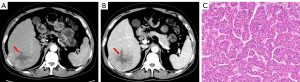

The final study sample comprised 122 patients with HCC [mean age: 53 years ±10 (SD); 102 males], among which 46 tumors (37.7%) were classified as MTM-HCCs. A lower proportion of MTM-HCC patients were over 55 years old [11 of 46 (23.9%) vs. 35 of 76 (46.1%); P=0.01]. The following characteristics were more prevalent in MTM-HCCs compared to non-MTM-HCCs: hepatitis B virus (HBV) or hepatitis C virus (HCV) infection [44 of 46 (95.7%) vs. 63 of 76 (82.9%); P=0.04], a-fetoprotein (AFP) levels ≥20 ng/mL [29 of 49 (63.0%) vs. 33 of 76 (43.4%); P=0.04], and microvascular invasion [24 of 46 (52.2%) vs. 25 of 76 (32.9%); P=0.04] (Table 1). Additionally, MTM-HCCs were shown to be more likely to exhibit substantial necrosis (Figure 2) on preoperative CECT [26 of 46 (56.5%) vs. 25 of 76 (32.9%); P=0.01]. Meanwhile, other preoperative CT semantic features did not show significant differences between MTM-HCCs and non-MTM-HCCs (Table 2).

This study developed ML-based models for the diagnosis of MTM-HCC utilizing CT semantic features and whole tumor histogram features, and evaluated the prognostic significance for HCC. The MTM-HCC as reported by Calderaro et al. (7) is significantly associated with poor prognosis, with higher early recurrence and overall recurrence rate (24). In our study, the MTM-HCC was observed in approximately 37.7% of HCC, in consistence with the report of Feng et al. (19). Statistically significant differences were observed between MTM-HCCs and non-MTM-HCCs in terms of patient age, HBV or HCV infection status, elevated AFP levels, microvascular invasion, and substantial necrosis. Furthermore, substantial necrosis was an independent predictor of MTM-HCC, as it reflects inadequate blood supply due to rapid tumor growth, indicating that the tumors were more aggressive, which had been confirmed by other studies (14,25,26).